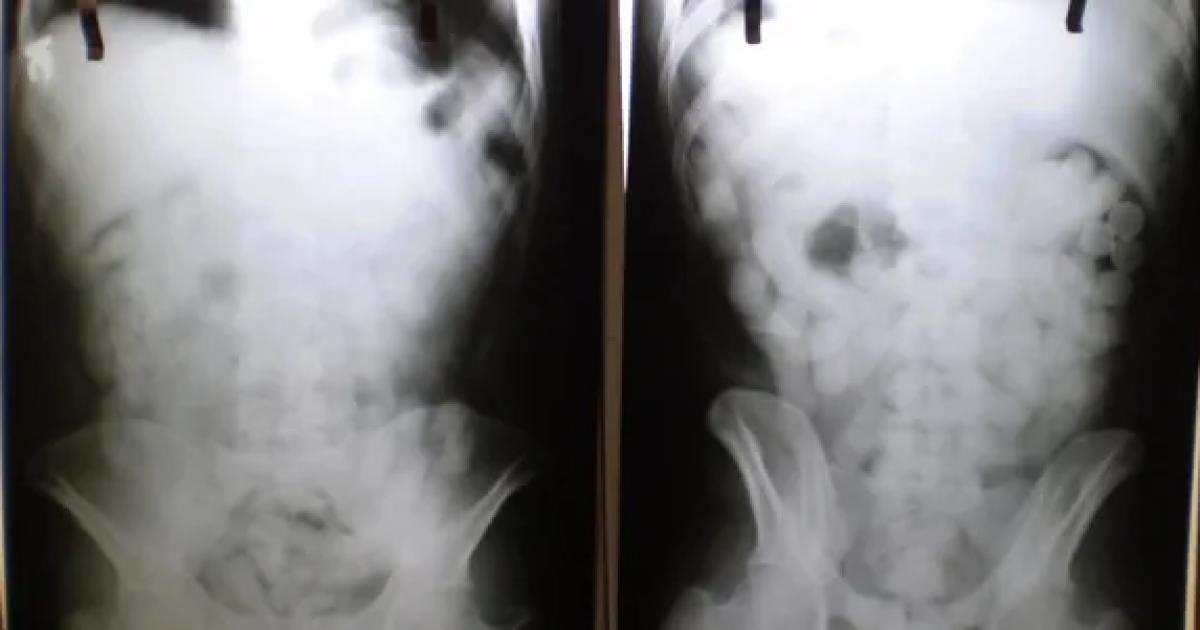

Tras un control con escáner corporal, se confirmó que transportaba múltiples cuerpos extraños en su interior. Fue inmediatamente internado en el Hospital de Ezeiza, donde permaneció bajo estricta vigilancia médica y policial durante cuatro días, período en el cual evacuó las 90 cápsulas que totalizaron 698 gramos de cocaína.